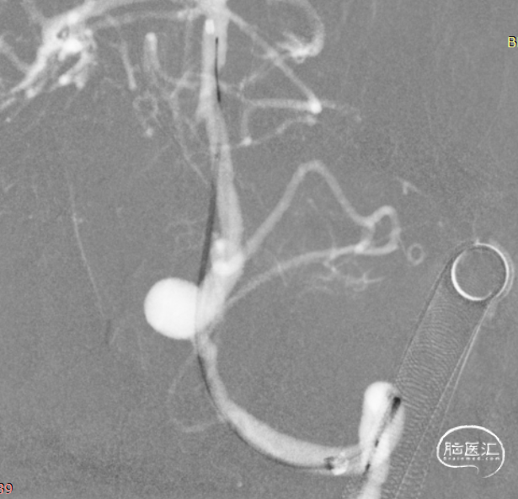

术前造影:

左颈。

手术设计方案:J-Tube™血流导向密网支架单独治疗动脉瘤。